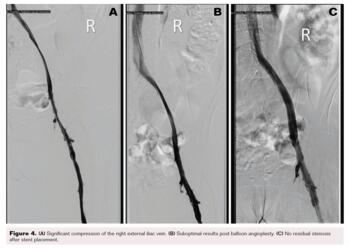

A 57-year-old woman with a history of severe rheumatoid arthritis and urothelial carcinoma of the bladder with a chronic urostomy in place was referred to our clinic for chronic right lower extremity pain and swelling. At the time of original presentation, she was experiencing symptoms for 2 years. Our initial workup with venous duplex US of the lower extremity showed patent veins with no evidence of thrombus; severe venous reflux disease was noted in the right greater saphenous vein (GSV) and small saphenous vein (SSV). After failed conservative management for several months with a graded compression stocking, leg elevation, and calf exercises, she underwent ablation of the GSV with Varithena (Boston Scientific), followed by ablation of the SSV a few months later with radiofrequency ablation. Despite ablation, swelling persisted, and 2 months after her vein ablation she presented with dramatically worsened lower extremity pain, swelling, and redness. US of the lower extremity showed occlusive DVT of the right CFV. We scheduled her for a right venogram with planned thrombectomy of the proximal acute DVT. Access was obtained from the right popliteal vein with US guidance. The vein was initially accessed with micropuncture because the popliteal vein caliber was exquisitely small. After access, the micropuncture sheath was upsized to 8 Fr. Contrast was injected through the 8 Fr sheath to obtain diagnostic images. The patient had 90% stenosis of the right CFV with a heavy thrombus burden and severe, diffuse compression of a small caliber right EIV of 70%. An IVUS catheter was advanced into the EIV and pulled back to confirm the degree of stenosis. This confirmed small-caliber central vein sizes. IVC measured 8.3 mm in the minor axis and 16 mm in the major axis, with a cross-sectional area of 112 mm2; EIV measured 7.4 mm in diameter and 65 mm2 in a cross-sectional area; and CFV measured 11 mm in diameter and 103.8 mm2 in a cross-sectional area (Figure 3). The patient underwent thrombectomy of the right CFV utilizing ClotHunter (Boston Scientific) with ZelanteDVT (Boston Scientific), with excellent clot debulking of 0% residual clot burden after thrombectomy. For the EIV, a balloon angioplasty was performed with a 12 x 80 mm Charger balloon (Boston Scientific), which did not result in reduction of the stenosis. A 12 x 140 mm Zilver Vena stent was placed in the common iliac vein to EIV and post-dilated with the same balloon with good results.

No residual stenosis was noted post procedure (Figure 4). At the end of the procedure, hemostasis of the popliteal vein was obtained with manual compression. On follow-up over the next 6 months, the patient’s edema slowly decreased and substantially improved, along with eventually improved pneumatic mechanical compression. Her pain symptoms completely resolved soon after the procedure.